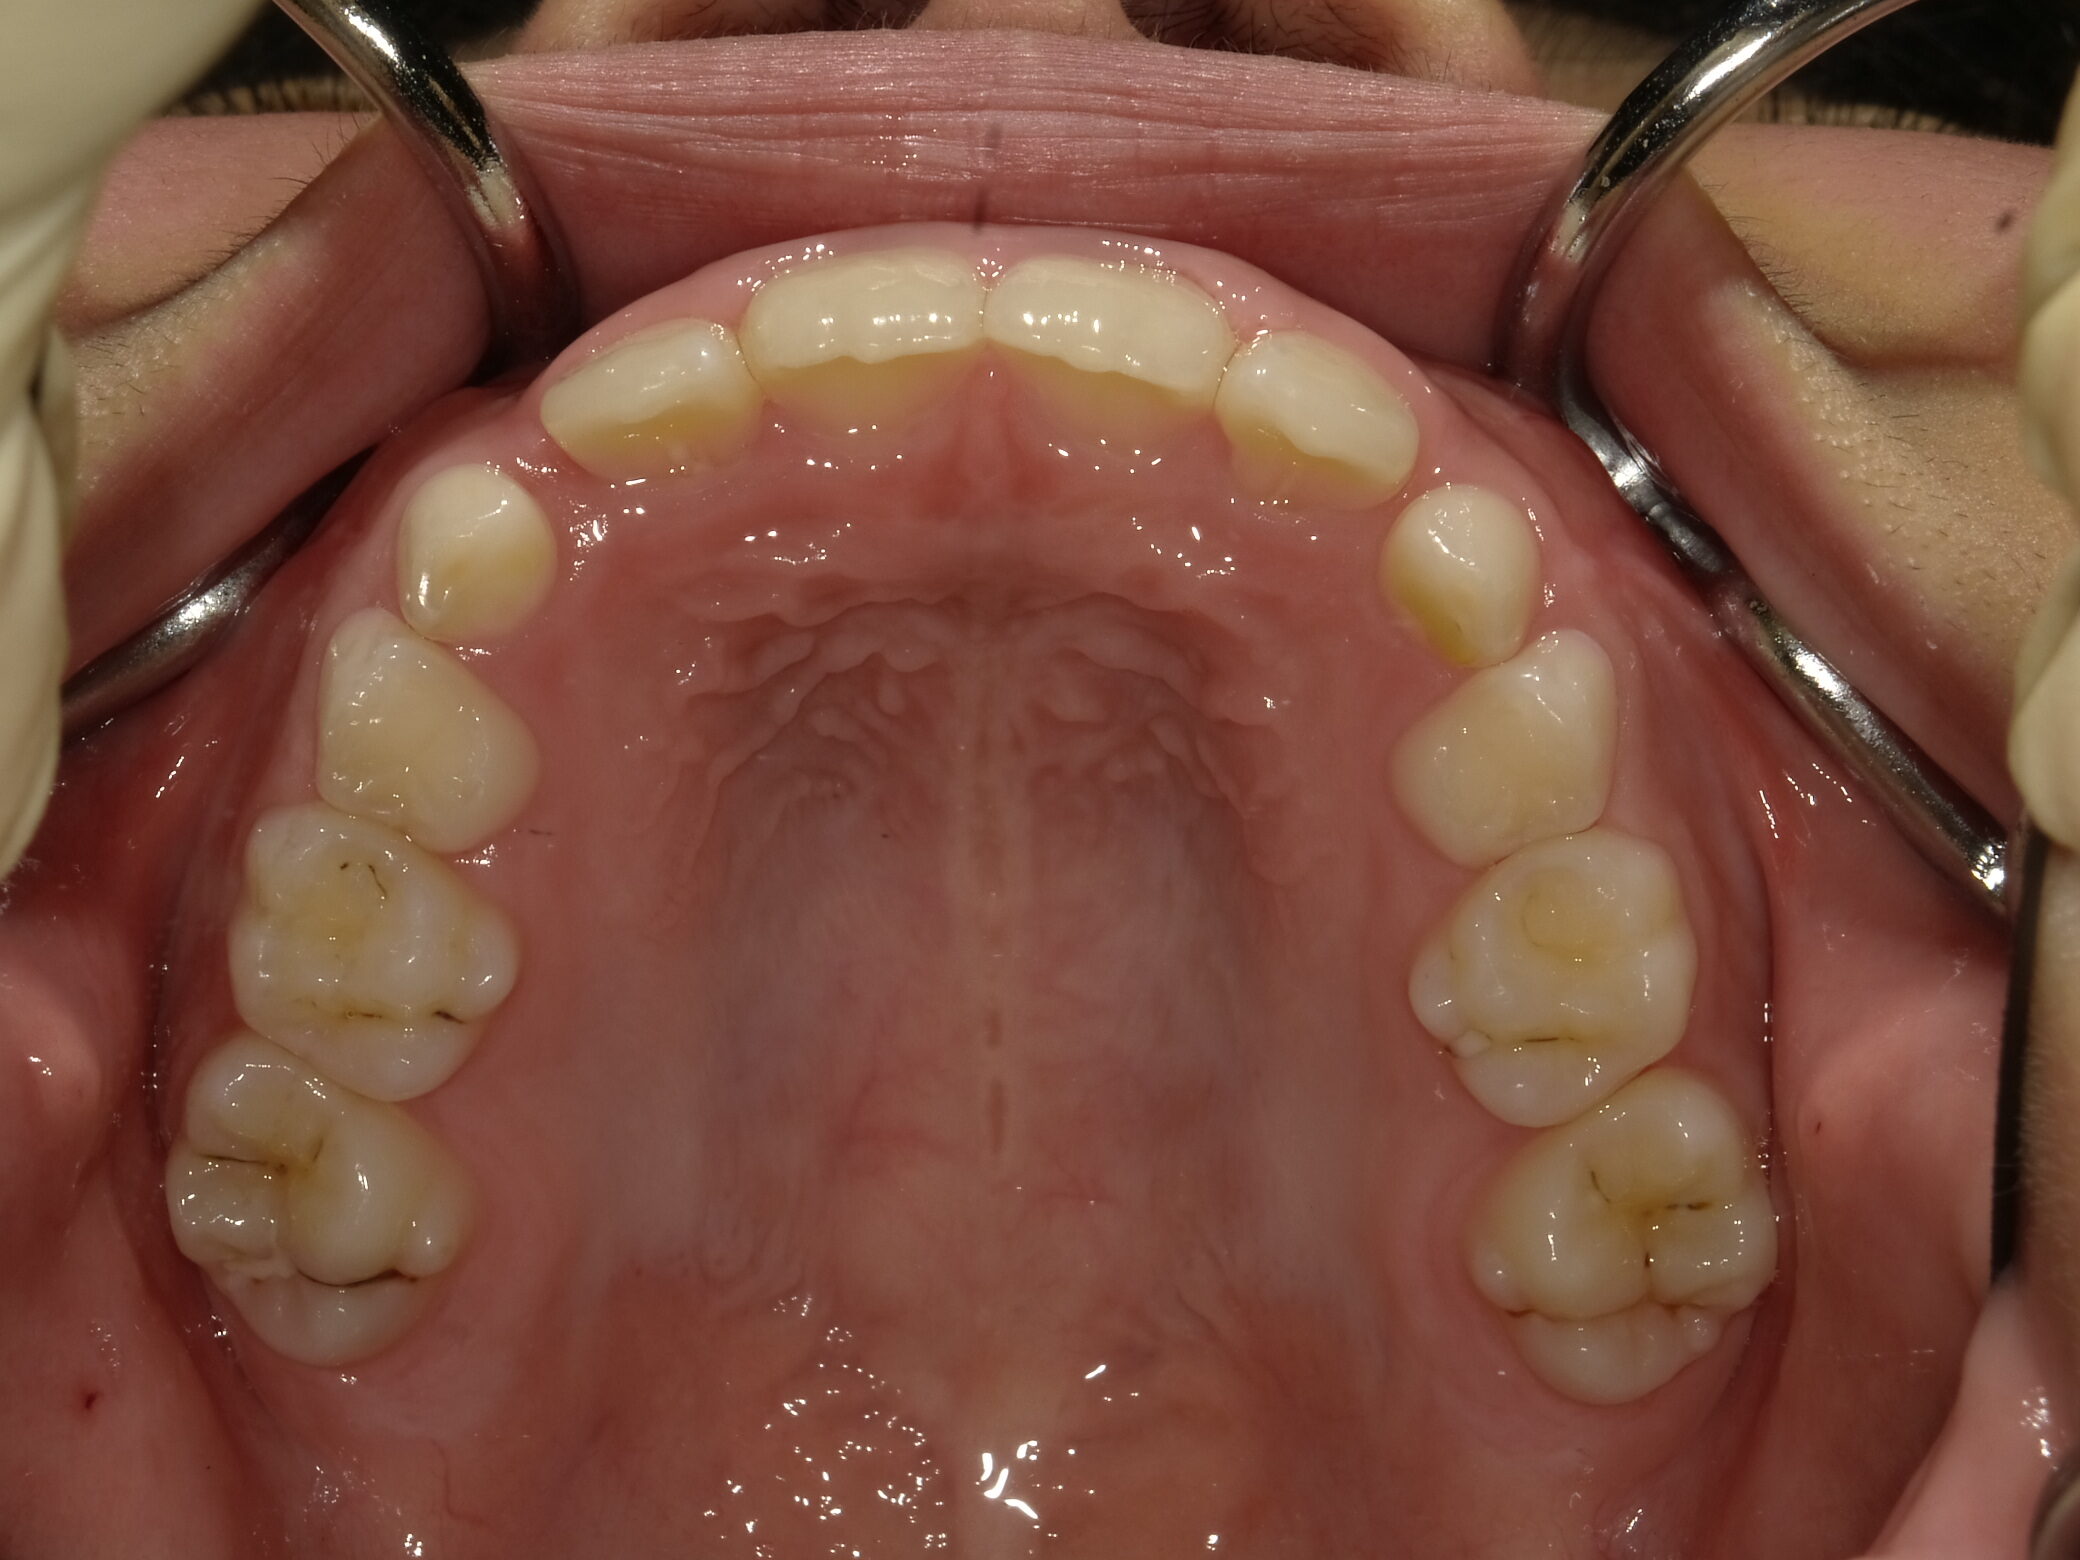

| 症例分類 | 交叉咬合 |

|---|---|

| 主訴 | 前歯がずれて咬んでいる |

| 年齢 | 9歳5ヶ月 |

| 性別 | 女性 |

| 抜歯部位 | なし |

| 使用装置 | 拡大装置、上顎前歯部のセクショナルアーチ装置、取り外し式保定装置 |

| 治療期間 | 1年2ヶ月 |

| 費用 | 相談料0円、検査料50,000円 動的矯正治療費330,000円 調整料6600円×15回分 保定装置料0円 |

| リスク・注意点 | 個々の歯の大きさに対して顎が小さく、歯が並ぶスペースが不足したために交叉咬合が生じています。これらを改善するために、幅の狭搾している歯列を側方に拡大した後、前歯を排列しました。

歯の動き方には個人差があり、予想された治療期間が延長する可能性があります。 治療中は矯正歯科装置が歯の表面に付いており、歯が磨きにくくなるため、むし歯や歯周病が生じるリスクが高まります。ハミガキを適切に行ってお口の中を常に清潔に保ち、さらに、かかりつけ歯科医に定期的に受診することが大切です。 矯正歯科装置の使用状況、定期的な通院など、矯正歯科治療には患者さんの協力が必要であり、それらが治療結果や治療期間に影響します。 治療の経過によっては当初予定していた治療計画を変更する可能性があります。 保定装置の装着時間が十分確保できない場合、歯並びや、咬み合せの「後戻り」が生じる可能性があります。 上下両側第二大臼歯の萌出を観察する必要があります。 |